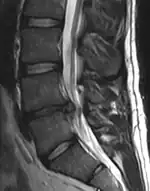

The lumbar (or lower back) region is the area between the lower ribs and gluteal fold which includes five lumbar vertebrae (L1–L5) and the sacrum. In between these vertebrae are fibrocartilaginous discs, which act as cushions, preventing the vertebrae from rubbing together while at the same time protecting the spinal cord. Nerves come from and go to the spinal cord through specific openings between the vertebrae, receiving sensory input and sending messages to muscles. Stability of the spine is provided by the ligaments and muscles of the back and abdomen. Small joints called facet joints limit and direct the motion of the spine.[35]

Imaging is indicated when there are red flags, ongoing neurological symptoms that do not resolve, or ongoing or worsening pain.[5] In particular, early use of imaging (either MRI or CT) is recommended for suspected cancer, infection, or cauda equina syndrome.[5] MRI is slightly better than CT for identifying disc disease; the two technologies are equally useful for diagnosing spinal stenosis.[5] Only a few physical diagnostic tests are helpful.[5] The straight leg raise test is almost always positive in those with disc herniation,[5] and lumbar provocative discography may be useful to identify a specific disc causing pain in those with chronic high levels of low back pain.[46] Therapeutic procedures such as nerve blocks can also be used to determine a specific source of pain.[5] Some evidence supports the use of facet joint injections, transforminal epidural injections and sacroiliac injections as diagnostic tests.[5] Most other physical tests, such as evaluating for scoliosis, muscle weakness or wasting, and impaired reflexes, are of little use.[5]